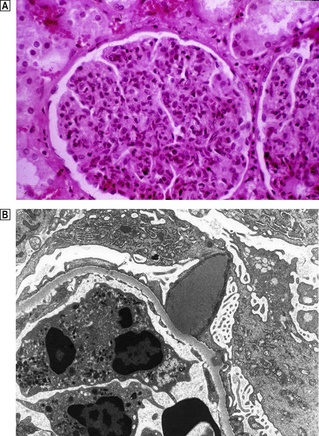

Histological features

Capillary wall thickening, without proliferation or inflammation, and characteristic spikes occur in all glomeruli (Fig. 21.7). There are granular immune deposits of IgG and C3 in the thickened capillary walls. Electron microscopy reveals immune complexes deposited on the outer aspect of the basement membrane beneath the epithelial cells and there is effacement of the foot processes. The epithelial cells overlying the deposits produce new basement membrane, forming the spikes seen light microscopically; this encircles the deposits which undergo degradation and lysis. Eventually the affected glomeruli become sclerosed.

image

Fig. 21.7 Membranous glomerulopathy. image Membranous glomerulopathy is characterised by thickened glomerular capillary walls. image Histological staining by a silver impregnation method reveals minute ‘spikes’ on the outer aspects of the capillary wall. image An electron micrograph shows the capillary wall to be thickened by the deposition of electron-dense deposits beneath the epithelial cells and between them new basement membrane corresponding to the ‘spikes’ seen histologically. image Immunofluorescence microscopy reveals granular deposition of IgG in the glomerular basement membranes, corresponding to the electron-dense deposits ultrastructurally.

Pathogenesis

The features of membranous glomerulopathy suggest a chronic immune complex disease, but the precise molecular target is still debated. Possibilities include glycoproteins (megalin) on the surface of the epithelial cells.